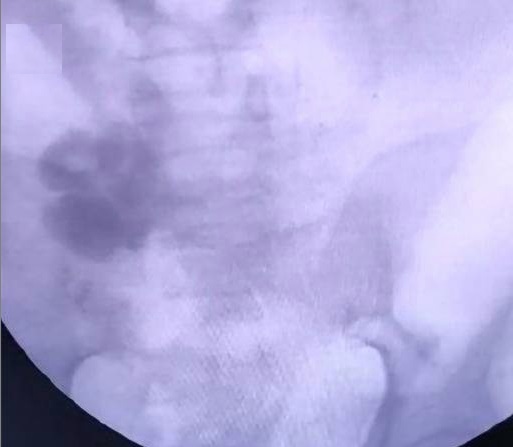

Based on this, few authors recommend concomitant embolization of variceal complex during TIPS (Figure (Figure4).

基于此,很少有作者建议在TIPS期间同时栓塞静脉曲张丛